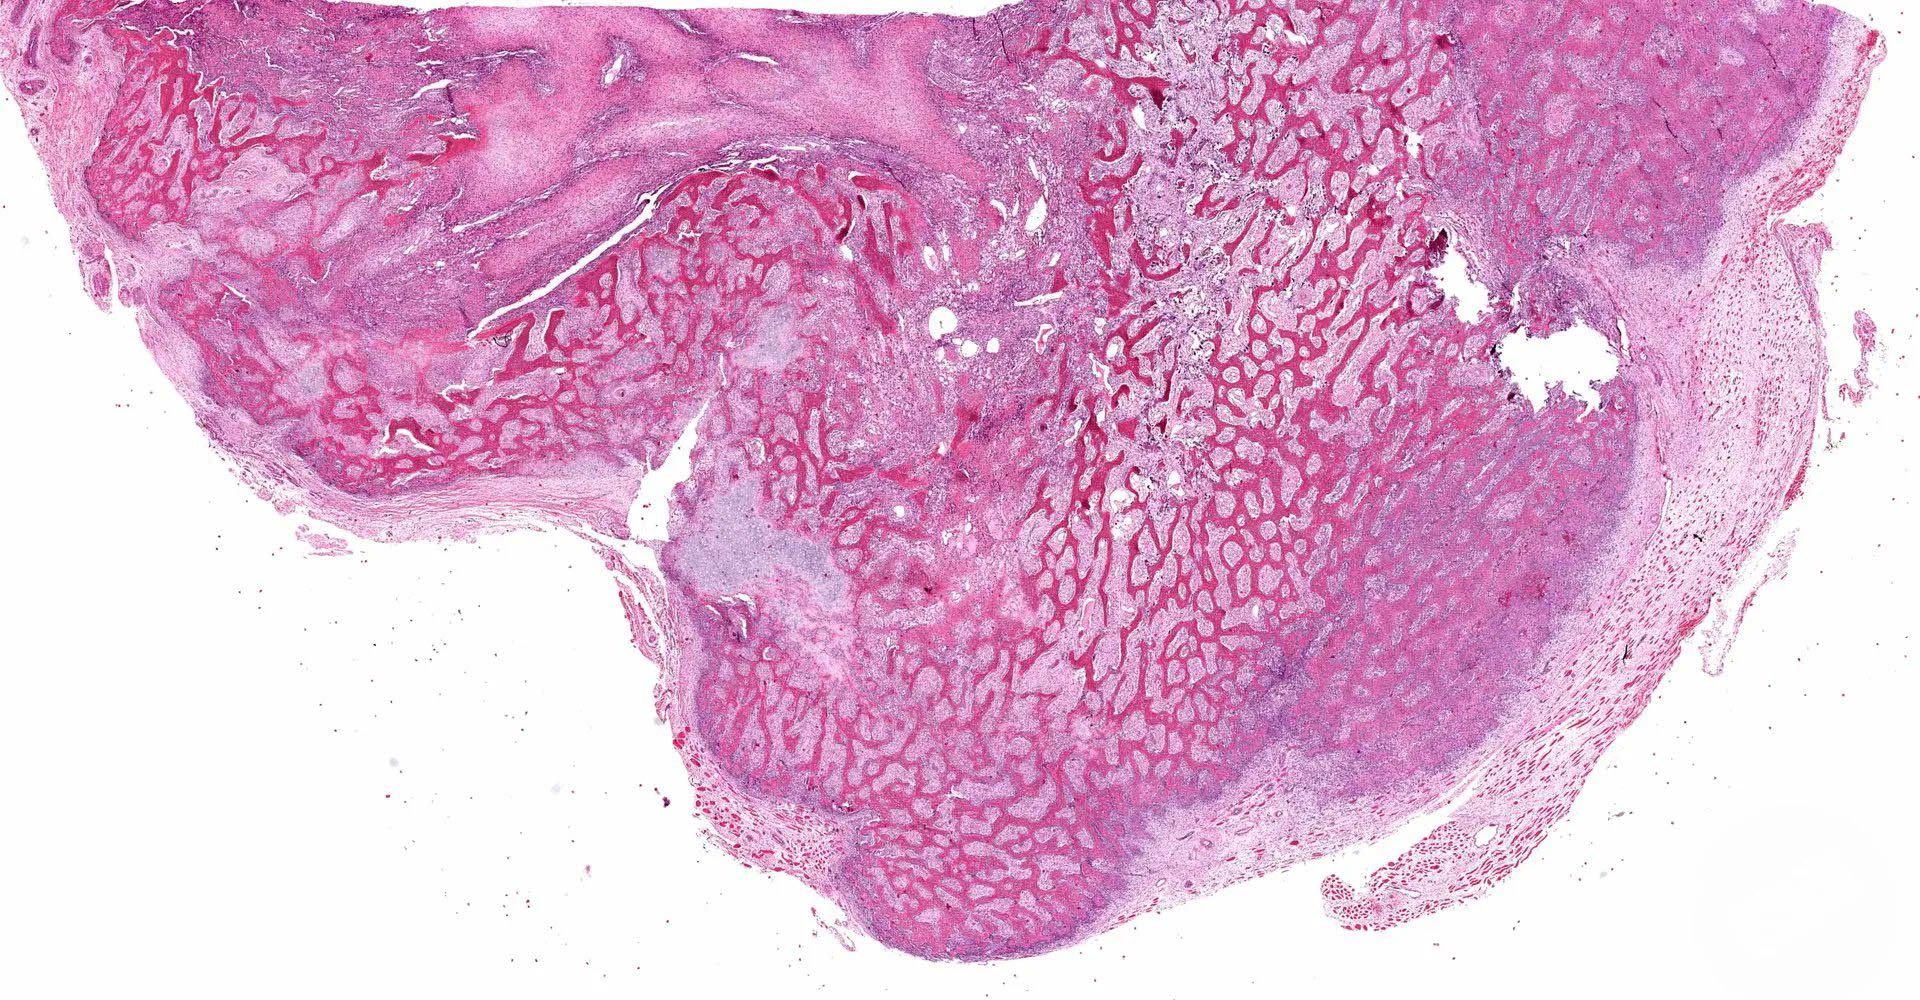

Gross description

- Well circumscribed mass with firm, gritty cut surface (Indian J Thorac Cardiovasc Surg 2020;36:657)

- Center of the lesion is usually soft, gelatinous or hemorrhagic

- Histologically, zonal pattern is characteristic with different degrees of cellular differentiation (inner zone, intermediate zone and peripheral zone)

- Peripheral zone:

- Osteoid undergoes calcification and leads to lamellar bone formation

- Islands of mature or immature cartilage may be present

- Extreme periphery / margin shows mature bone with osteoblastic rimming and little to no pleomorphism

- Lesion is separated from the normal tissue (muscle) by a zone of loose, myxoid fibrous tissue

- Late, mature stage (> 8 weeks):

- Mass is mostly composed of mature bone

- Very old lesions show only lamellar bone separated by fibrovascular stroma, mimicking osteoma